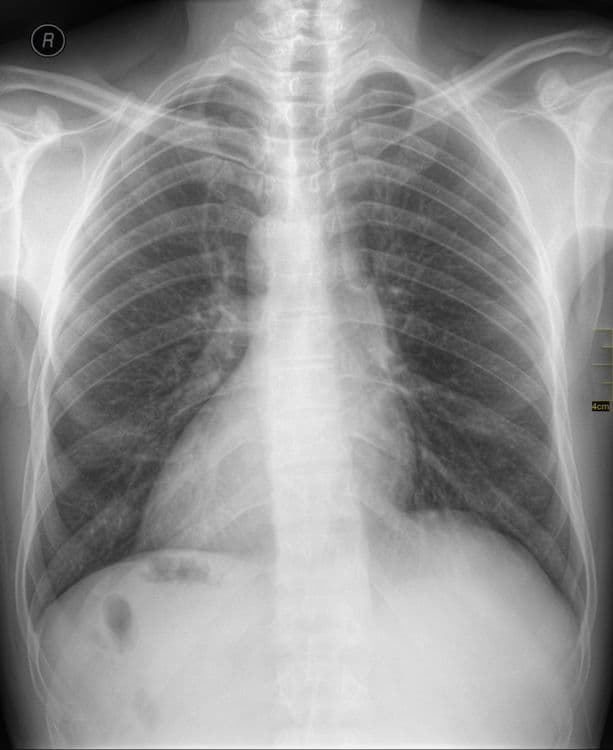

साधारणपणे माणसाचं हृदय डाव्या बाजूला असतं, पण ‘Dextrocardia’ हा आजार असलेल्या माणसाचं हृदय उजव्या बाजूला असतं. या आजारावर आधारित आपल्याकडे इम्रान खान आणि संजू बाबाचा ‘लक’ नावाचा सिनेमा येऊन गेला.

मंडळी, या प्रकाराला शास्त्रीय भाषेत Situs inversus म्हणतात. ही एक अवस्था असून यात माणसाच्या शरीरातील प्रमुख अवयव उलट्या दिशेत असतात. एकूण लोकसंख्येच्या अवघ्या ०.०१% एवढ्याच लोकांमध्ये ही अवस्था सापडते. बऱ्याचशा लोकांना आपल्या शरीरात असे उलटे अवयव आहेत हे माहितीच नसतं. त्याचा शरीरावर विपरीत परिणाम देखील होत नसतो.